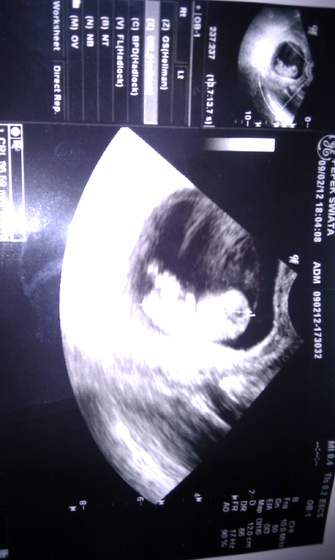

I ja po wizycie. Maleństwo rośnie- ma już 3,5cm :D Machało do nas rączkami i nóżkami i pocierało sobie buziola łapką. Piękny widok! Moje krwawienia to nadżerka- lekarz delikatnie mnie zbadał, a krwawienie jakby mi coś urwało....

Dostałam kolejne badania- hiv, hcv, różyczka i coś tam jeszcze. 22.02 mam usg genetyczne.

A oto i Małe:

jestesmy :) maluch ma 2,5cm :) 180 uderzen sserducha :) jest piekny:) widzielismy nozki i raczki a i ruszal dupka:) ale chwileczke tata nim podszedl to sie zawstydzil i przestal:) uslyszelismy pieknie bijace serduszko ,i wsio jest oki Aha roznica jest rowny tydzien wiec kropek ma 8t6d , jedyne co to ten zawiazek z ktorego bedzie lozysko uciska na scianke czy szyjke czy cosik tam takiego i moga byc krwawienia do duuzej ciazy nawet i zeby sie nie martwic nimi . mam szybko pozbyc sie przeziebienia bo ono najbardziej mu szkodzi :( lece sie wygrzewac dzieki za kciukasy